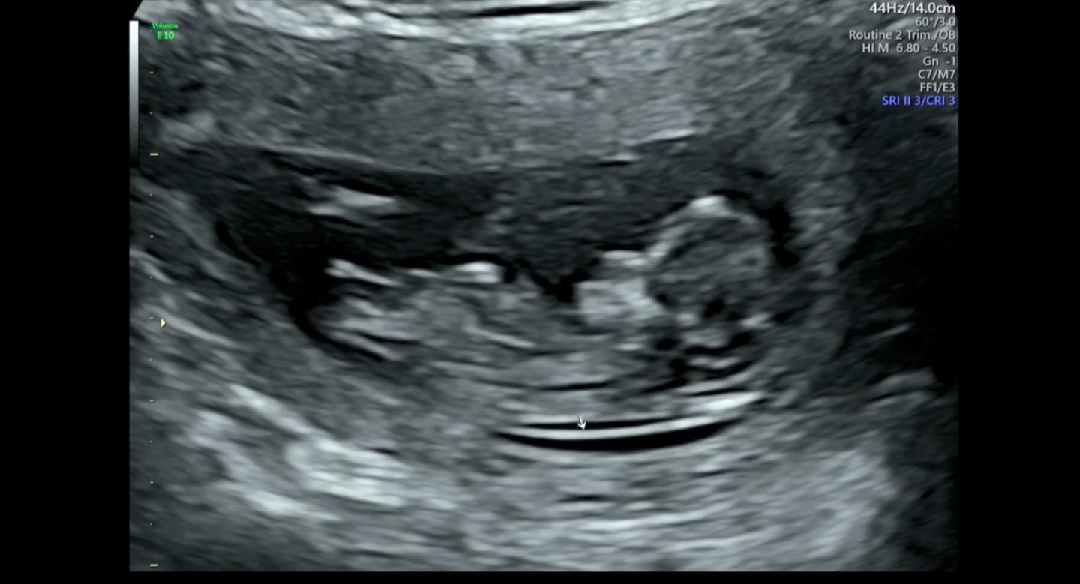

12주차 초음파인데 성별 뭐같나요 고수분찾아용

내일 성별 보러가긴하는데 그래도 궁금합니다!

고수는 아니지만 공주님인것 같아요👧🏻

딸요 ㅎㅎ